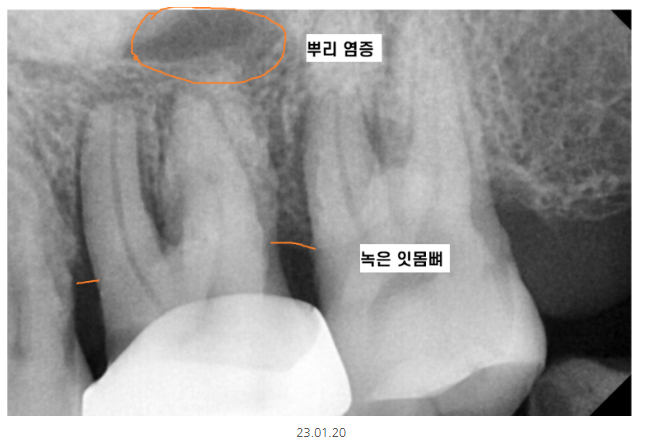

230120

1차적으로 육안 검사를 시행하긴 하지만

눈으로 볼 수 없는 부분이 있습니다.

뿌리 쪽 부분이죠~

만성 염증

그러니까 치아가 오랫동안 염증으로

안 좋은 경우에는

잇몸뼈가 녹고 뿌리 끝에 염증이 있더라도

안 아프신 경우가 많습니다.

만성이니까요.

눈으로만 검사해서는 놓칠 수 있는 부위가 있기에

x-ray를 촬영하는 거랍니다~!